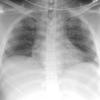

Blunt Chest Trauma

Pneumothorax

Album: Pneumothorax